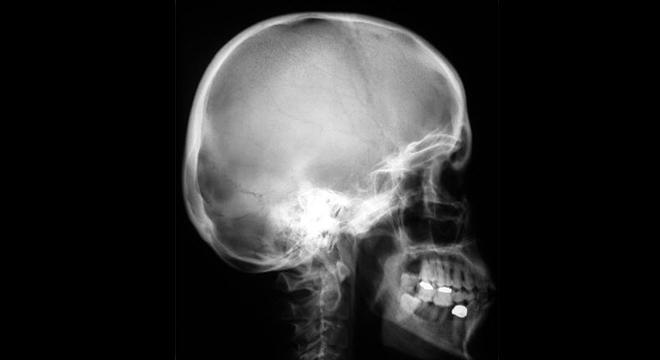

Gehirnerschütterung: Röntgenaufnahme des Schädels

• Röntgenaufnahme des Kopfes zum Ausschluss einer Knochenverletzung am Kopf und eventuell eine Computertomographie bei Verdacht auf Hirnschädigung oder Blutung